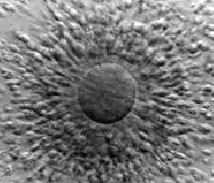

Un numar de celule incojoara ovulul care in prealabil a fost aspirat dintr-un

folicul matur.